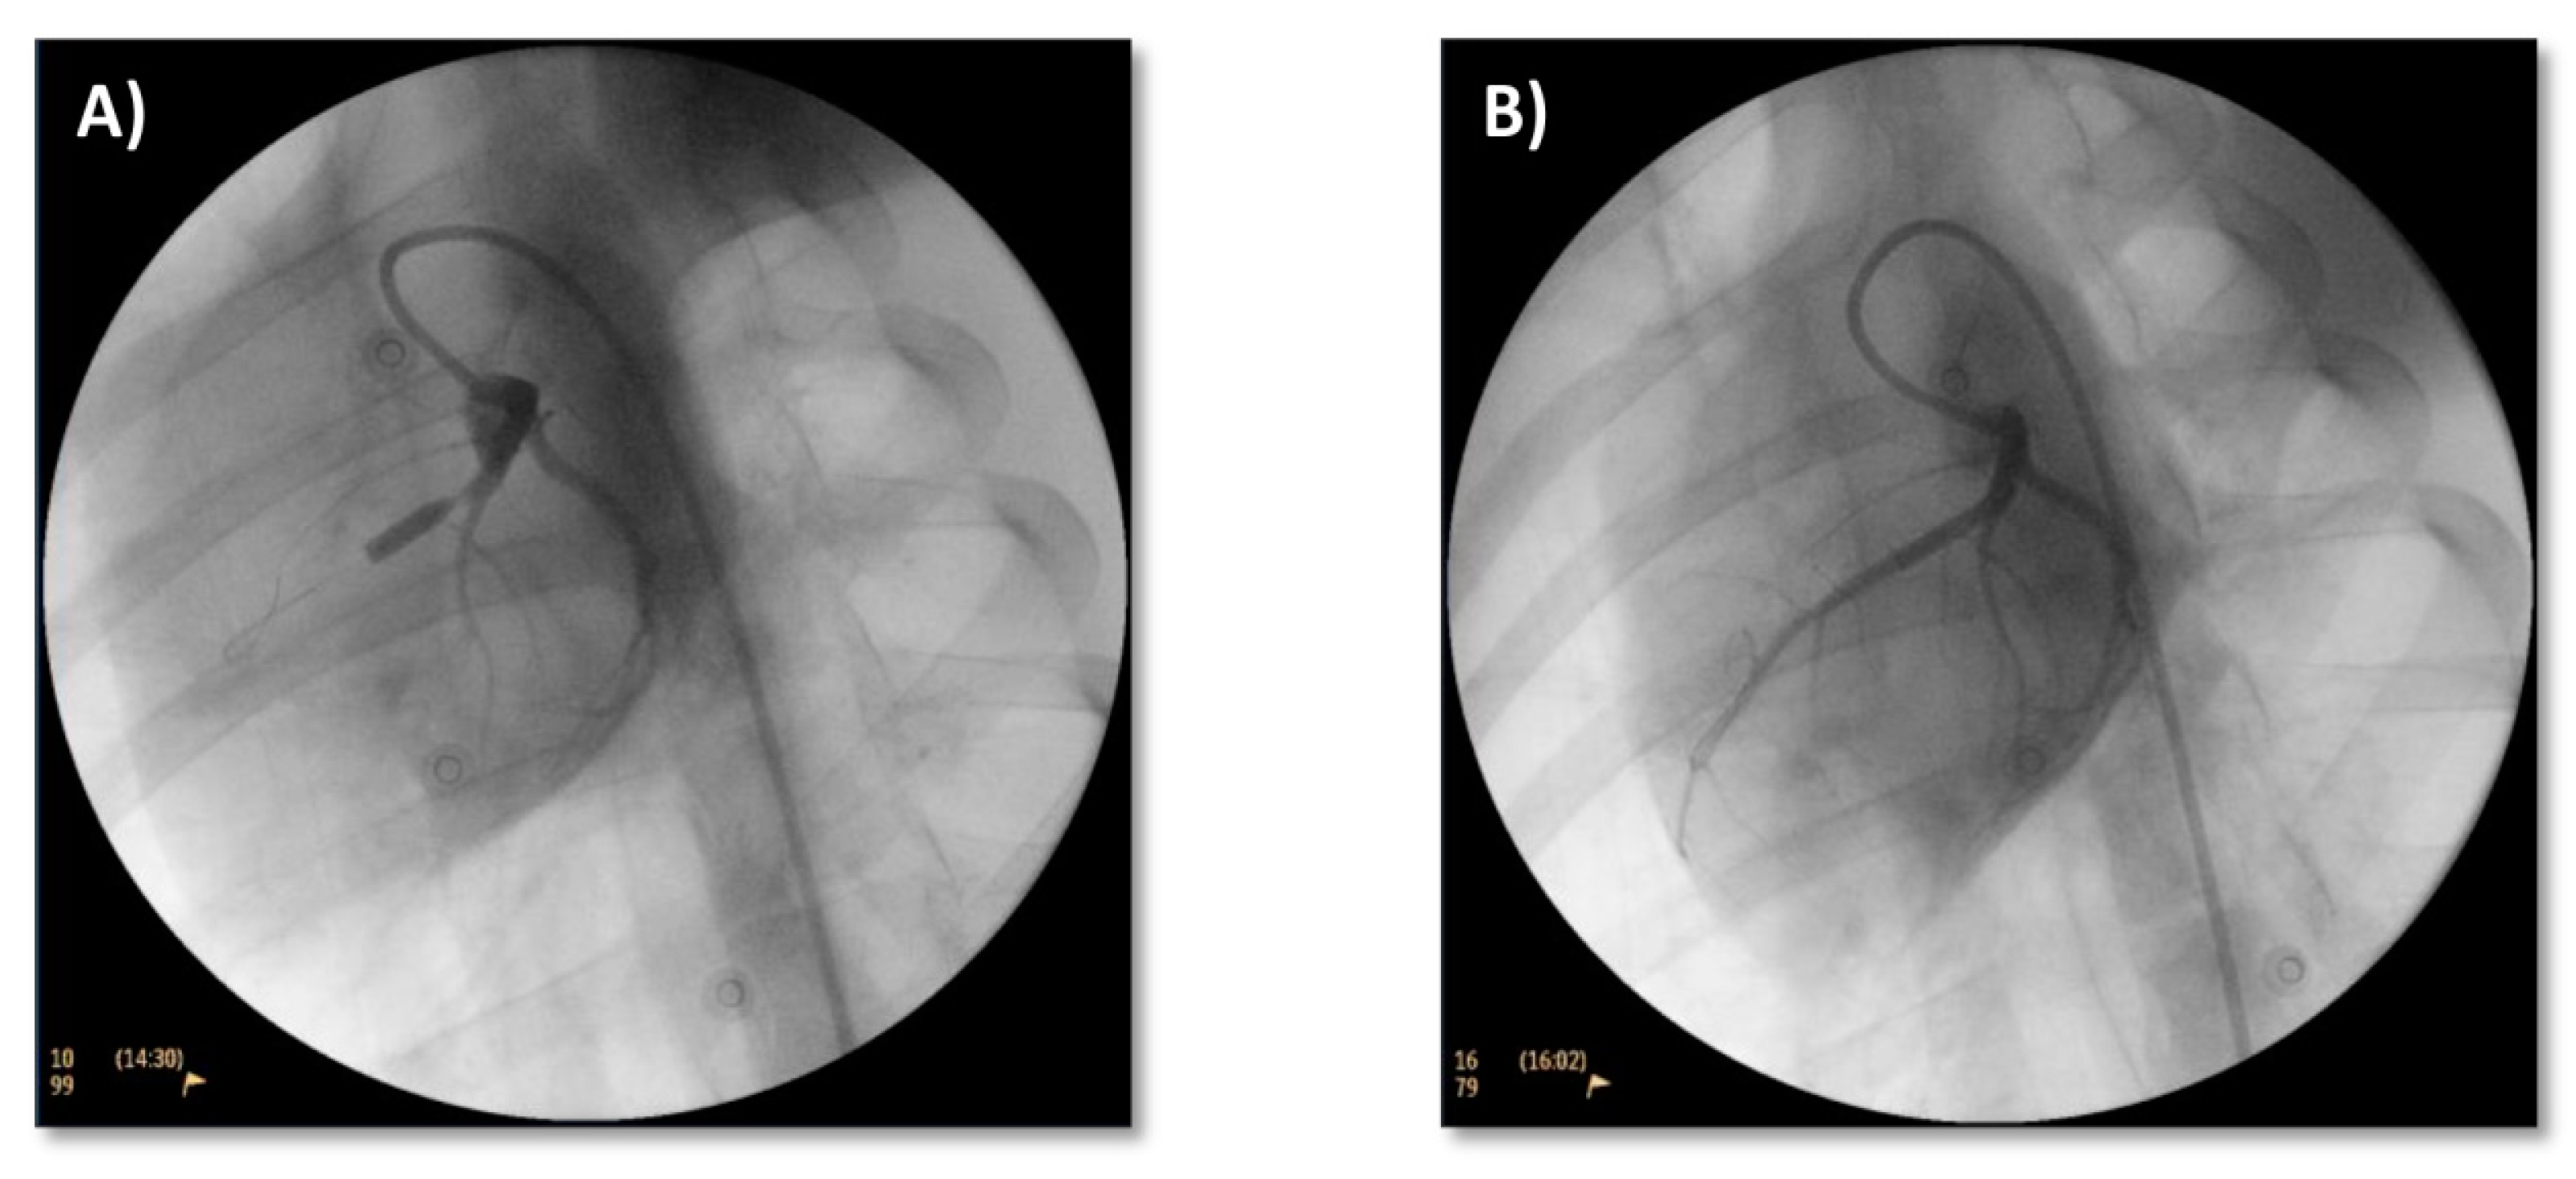

3.1. Model Induction

3.2. Treatment

3.2.1. Coronary Flow and ECG